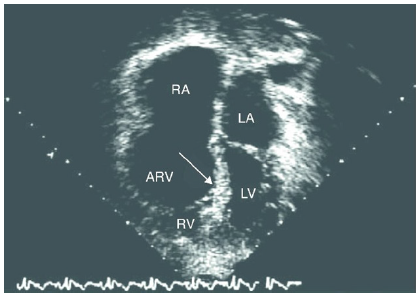

Paciente, 33 anos, com quadro de intolerância

aos esforços e palpitações por episódios de

taquicardia supraventricular, apresentou um

episódio de acidente vascular cerebral há

duas semanas. Em relação à imagem a seguir

e ao caso clínico apresentado, assinale a

alternativa INCORRETA.